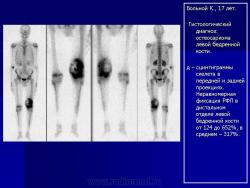

Телеангиэктатическая остеосаркома - редкий (составляет около 4% всех остеосарком) вариант остеосаркомы, характеризующийся наличием кист, заполненных кровью. При рентгенологическом исследовании обычно выявляется полностью литическое поражение без признаков склерозирования, интенсивное вздутие кортикальной пластинки и ее деструкция, часто обнаруживаются периостальная реакция и распространение патологического процесса в мягкие ткани. Гистологическая диагностика телеангиэктатического варианта остеосаркомы может быть относительно несложной при наличии атипичного остеогенеза и высокой степени анаплазии клеточных элементов. Однако довольно часто, особенно у детей и подростков, диагностика вызывает значительные трудности, так как эта остеосаркома, в основном, представлена высокодифференцированным вариантом. Последний отличается тем, что опухолевые клетки определяются только в области выстилки кист и полостей опухоли, злокачественные клетки характеризуются низкой степенью анаплазии, опухолевый остеоид обнаруживается лишь при целенаправленном исследовании серийных срезов, встречаются участки ткани, в которых клеточные элементы и остеоид не имеют признаков атипизма и микроскопическая картина полностью соответствует аневризмальной кисте кости, в связи с чем не исключена диагностическая ошибка при исследовании небольшого количества материала, особенно биопсийного. Относительно медленное развитие опухоли, обычно чисто литическое поражение кости, сходство рентгенологической картины с аневризмальной кистой или гигантоклеточной опухолью кости также способствуют постановке неверного диагноза.